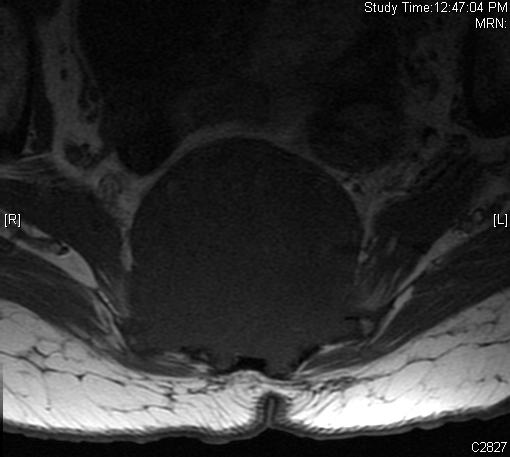

MRI (Fig. 4-10)

• Destructive bone lesion

• Isointense or hypointense on T1W (Fig. 4-5)

Fig. 4-10: MR image of a chordoma shows a destructive bone lesion in the sacrum that is hypointense on T1W images, hyperintense signal on T2W and enhancement of the lesion after gadolinium.